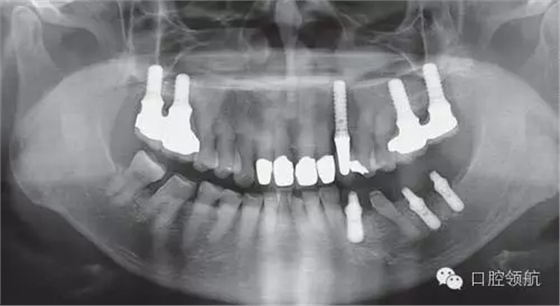

利用曲面斷層及CBCT檢查埋入部位情況,雖未出現(xiàn)與主訴相關(guān)的神經(jīng)損傷,但無(wú)意中卻發(fā)現(xiàn)了種植體的舌側(cè)穿孔(圖1、圖2)。

圖1 術(shù)后的曲面斷層影像。